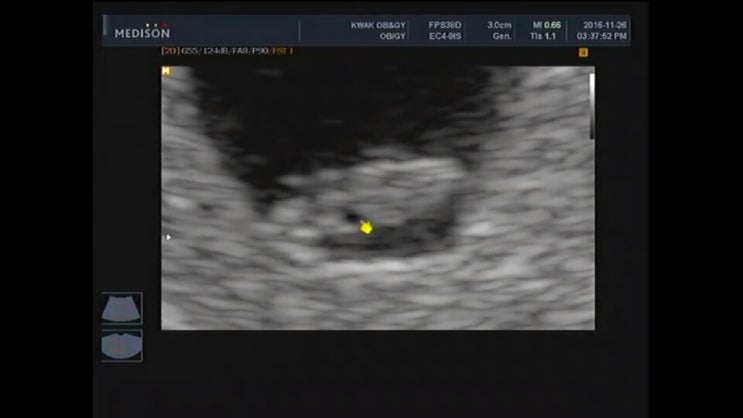

[임신 6주] 신혼 3년 차, 비단이를 만나다

16년도에는 내게 유독 많은 일들이 있었다. 직장을 그만두었고, 3개월 휴식 끝에 다니던 회사를 다시 복직...

[임신 8주] 젤리 곰 같은 너